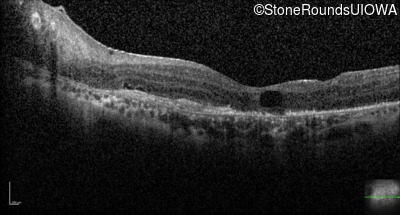

Optical Coherence Tomography - Left - 20/160

Exemplar / OCT Stack